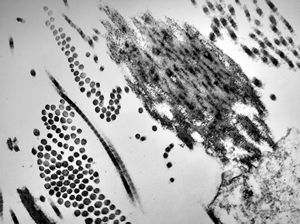

F, 24y. | molluscum contagiosum … virions

F, 24y. | molluscum contagiosum

F, 24y. | molluscum contagiosum

F, 7y. | molluscum contagiosum … virions

F, 7y. | molluscum contagiosum … virions

F, 24y. | molluscum contagiosum … virions